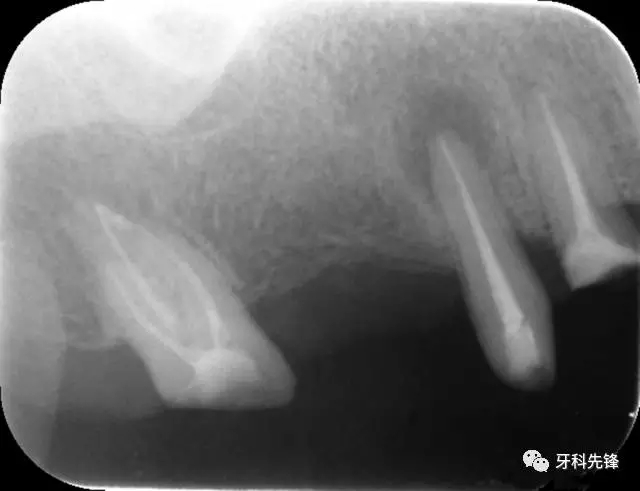

圖1 術(shù)前X光片

X 示:15  根管透射,根尖有陰影

14  根管阻射,恰填,無異常

46  根管阻射,恰填,根分叉骨密度降低,近中根尖陰影較大